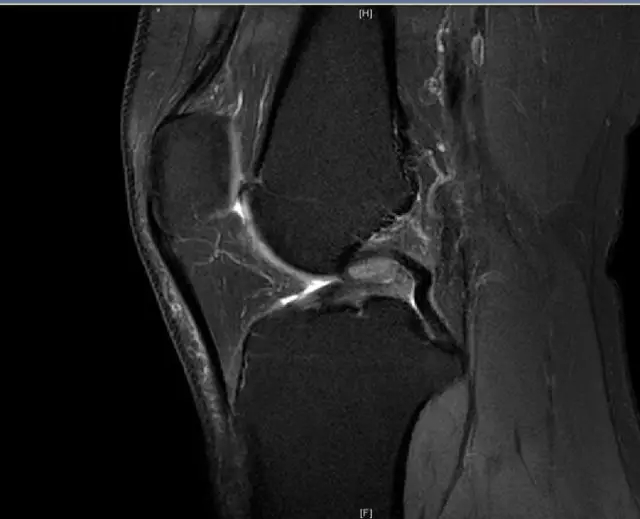

前交叉韧带断裂,外侧半月板后角撕裂

从此片我们可以看到前交叉韧带的上止点高信号,前交叉韧带角度增加,后交叉韧带的夹角增大,从这个层面可以看到外侧半月板边缘不清楚不完整质地不均一,混杂有高信号的改变,并且内部有一些裂隙,从这个层面我们可以看到前交叉韧带的下止点相对比较完整,而这个层面上止点信号异常,韧带松弛并且有大量的渗出病变,缺乏张力。这个层面也可以看到髁间窝这个部位凸起,看不到应有的上止点信号。所以这个病例我们需要考虑前交叉韧带断裂,外侧半月板后角撕裂。